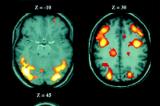

Դեմենցիան (dementia) ձեռքբերովի թուլամտությունն է, նախկինում ձեռք բերած գիտելիքների և պրակտիկ հմտությունների այս կամ այն աստիճանի կորստով և նորերի ձեռք բերման դճվարացմամբ կամ անհարինությամբ, ճանաչողական...

Սա առաջնային դեգեներատից դեմենցիա է, որն ուղեկցվում է հիշողության խանգարման, մտավոր գործունեության և այլ բարձրագույն կեղևային ֆունկցիաների խանգարման հարաճմամբ և հանգեցնում է տոտալ թուլամտության։ Սկսվում է 50 տարեկանից հետո...